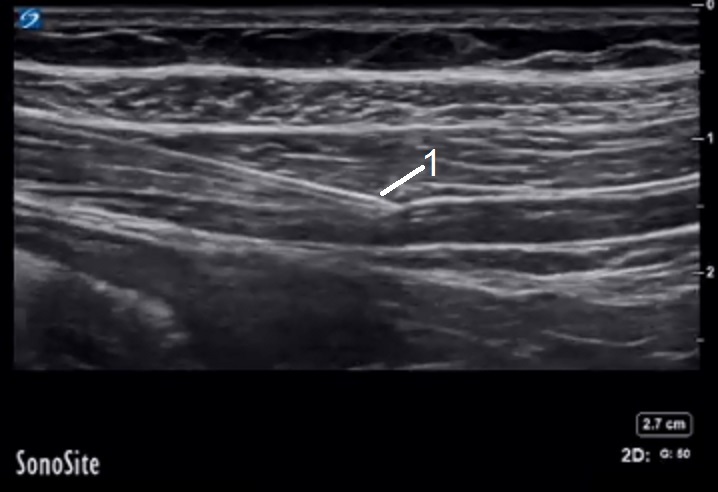

TAP Block 3 Image

Needle